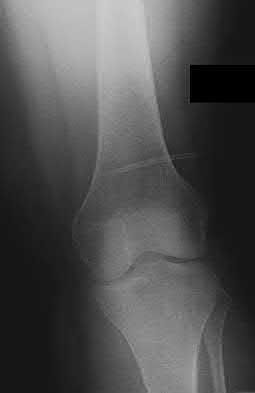

The safe zone for tibial nail placement as seen on radiographs is just medial to the lateral tibial spine on the anteroposterior radiograph and immediately adjacent and anterior to the articular surface as visualized on the lateral radiograph.

Tornetta et al specifically located the safe zone for nail entry in a study using fresh frozen cadaver knees. The authors found that the safe zone for nail placement is located 9.1+/-5 millimeters lateral to the midline of the plateau and three millimeters lateral to the center of the tibial tubercle. The width of the safe zone averaged 22.9 millimeters and was as narrow as 12.6 millimeters.

The starting point of the of the nail can be best viewed on the lateral knee radiograph, an example of which is shown in Illustration A. Illustration B shows the "sweet spot" for nail insertion as defined by Tornetta.